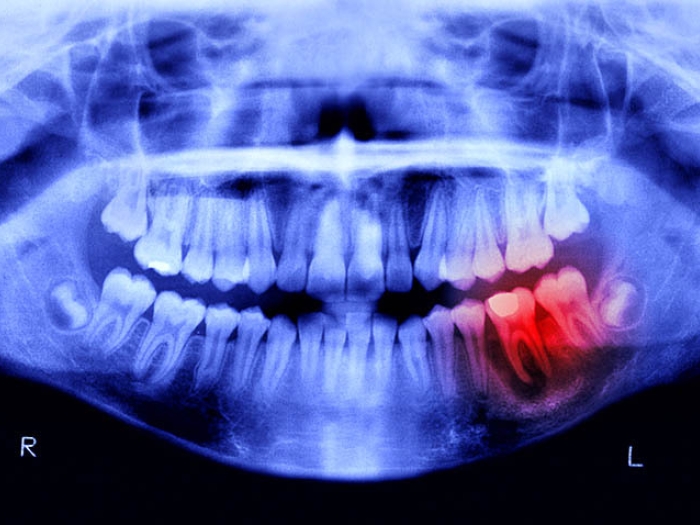

dental xray with red spot noting infection

Health Lab

Ouch: Patients Prescribed Opioids After Tooth Extraction Report Worse Pain

Dental patients who receive opioids after getting a tooth pulled have no less pain, and no more patient satisfaction, than those who receive non-opioid painkillers.